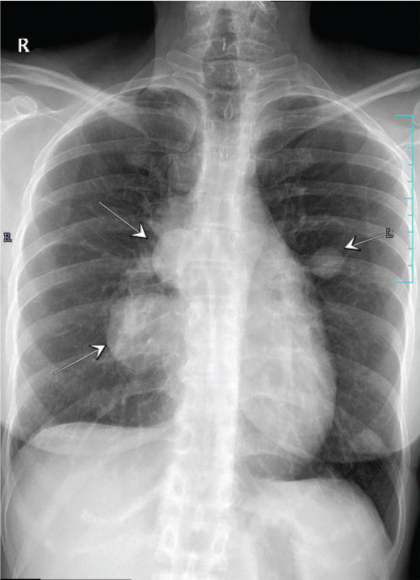

A 37-year-old Indian woman, presented with severe neck pain radiating to the arms, in 2007 at the age of 27 years. Magnetic Resonance Imaging (MRI) cervical spine revealed an enhancing epidural soft tissue lesion in the cervical spinal canal extending from C4-T1 level with abnormal signals in C5, C6, C7 vertebral bodies. Biopsy was suggestive of Primitive Neuroectodermal Tumour (PNET)/extraskeletal Ewing’s sarcoma. Her initial metastatic work up including bone marrow and skeletal scintigraphy was negative. She had an upfront debulking surgery following which her neck pain subsided. Thereafter, she was administered adjuvant chemotherapy with EURO Ewing protocol followed by consolidative radiation of 5000 centigray (cGy) in 25 fractions to the site of primary disease which she completed in late 2008. Three years later she presented in December 2011 with progressive cough and shortness of breath of one month duration. Computed Tomography (CT) scan of chest revealed right sided moderate pleural effusion and multiple pleural nodules. Her pleural fluid cytology was positive for malignant cells. She was administered three cycles of salvage chemotherapy with ifosfamide, carboplatin and etoposide. She attained a very good partial response and therefore was taken up for high dose chemotherapy and Autologous Stem Cell Transplantation (ASCT) in early 2012. She was given conditioning with busulfan-melphalan. She achieved complete remission and remained on close follow up surveillance for next 28 months. She presented in mid 2014 with persistent cough of two weeks duration. Chest X-ray and Positron Emission Tomography (PET-CT) showed bilateral canon ball lesions in both lungs [Table/Fig-1]. In view of her young age and good performance status, she was initiated on salvage chemotherapy with gemcitabine and docetaxel. She completed six cycles of the same and achieved radiological complete remission. Due to multiple recurrences, in an attempt to prolong her disease free interval, she was initiated on maintenance chemotherapy with cyclophosphamide 50 mg Once a Day (OD) and etoposide 50 mg OD (14/28 days). At the time of reporting she has completed 32 months of maintenance chemotherapy and continues to be in complete remission as evidenced by surveillance chest X-ray and PET-CT [Table/Fig-2]. She leads a fully active life.

Bilateral canon ball lesions in lungs clearly visible in chest X-ray (marked by white arrows).